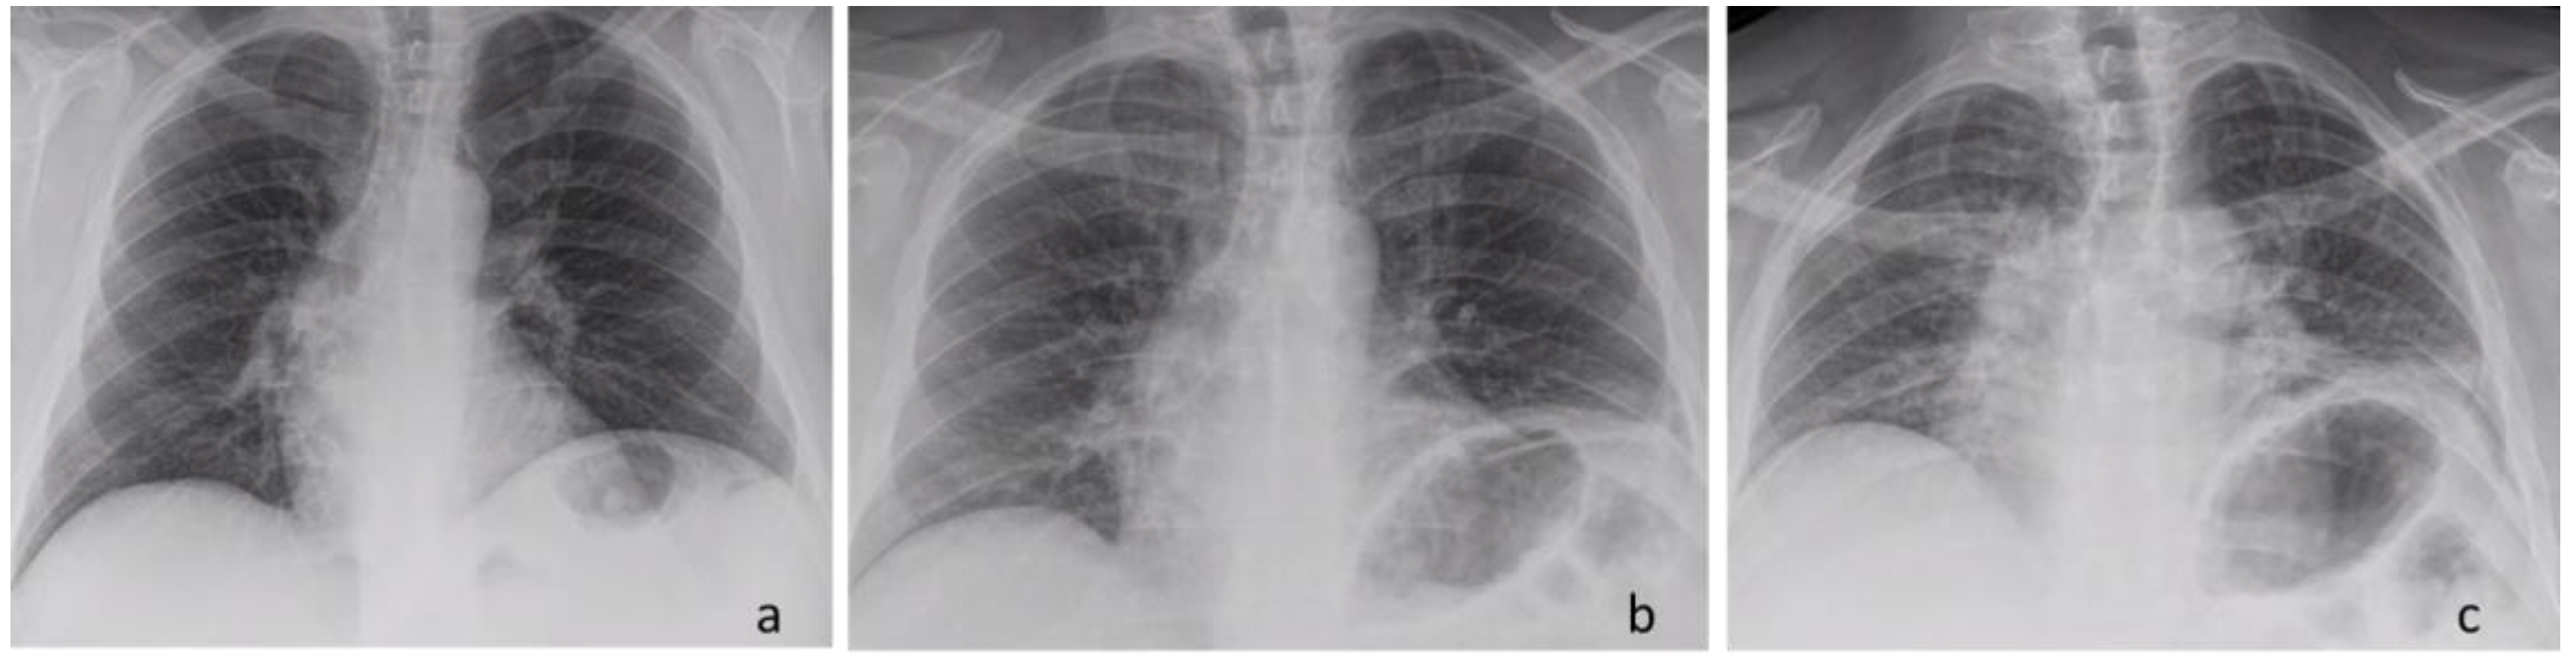

Figure 5.

Chest X-ray: Pre-operative finding—inspiration view (a). Post-operative finding—inspiration view (b). Post-operative finding—expiration view (c).